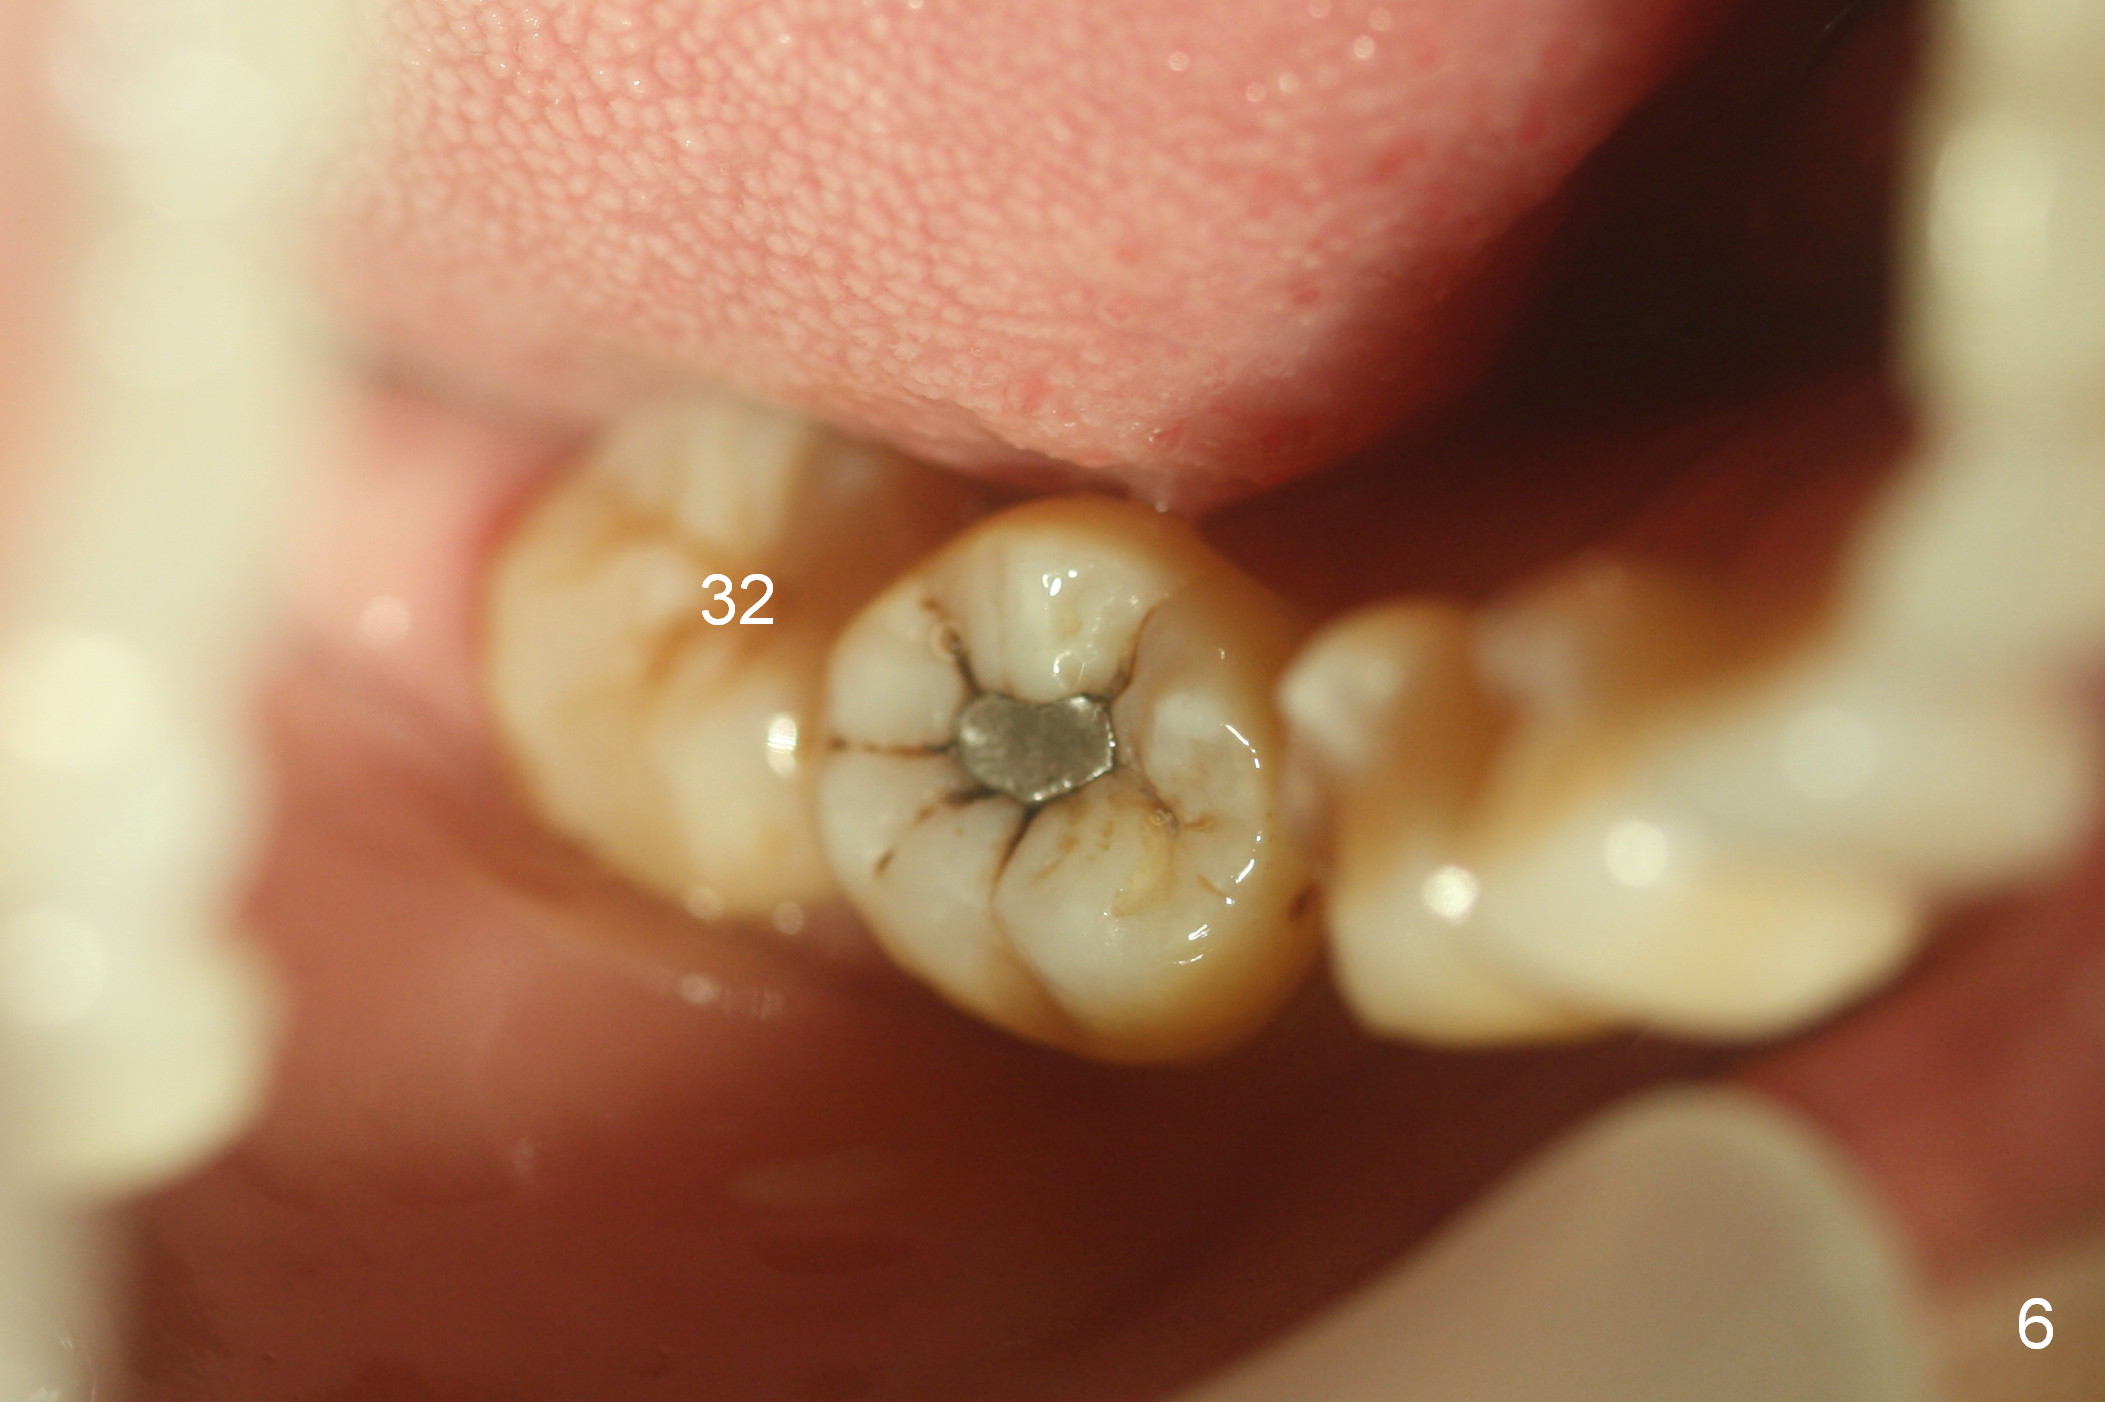

Show the patient that the tooth #31 is severely mesially tilted with reduction in the mesiodistal width for implant placement (Fig.5,7). The tooth #32 is severely malpositioned (linguoversion, Fig.6). It is extremely difficult to gain space for the implant without #32 extraction.